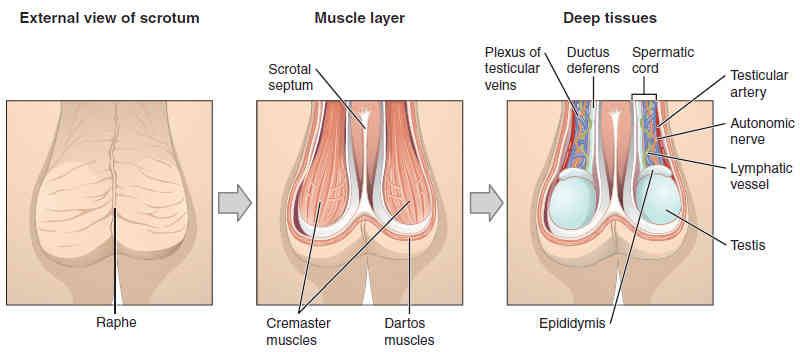

This page is under construction. For now, it is just a resource of the images found in the OpenStax Anatomy and Physiology Handbook. It wil slowly change into a revision tool. Each slide has a number. Use this to refer to the slide. When completed, it will have an unlabelled section, with labelled slides in parallel. On the unlabelled slides, write your answer and use the labelled slide to assess yourself. Keep track by also noting the number on each slide. Improvement at each attempt is important, more so than full marks on a first attempt.